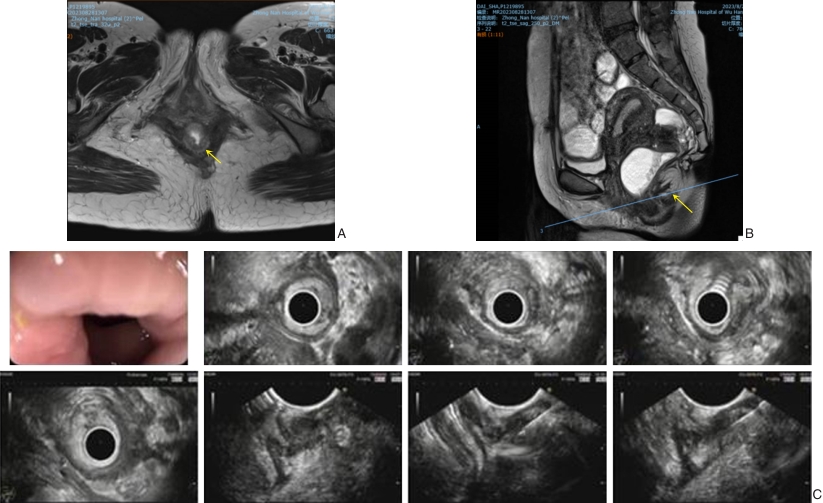

图1 患者术前影像资料 A-B:分别为盆腔增强MR T2轴位及T2矢状位,提示直肠中段管壁局限性环形增厚伴管腔明显狭窄,下缘距离肛缘约75 mm,病变范围长约20 mm,病灶与子宫后壁分界不清,局部子宫后壁呈混杂信号,内见小点状T2高信号影,其中橙色箭头指示处为病灶;C:EUS示直肠距肛门8 cm可见环形狭窄,内镜可勉强通过,探头置直肠狭窄处可见直肠右侧壁不均匀增厚,管壁层次结构消失,最厚处10 mm,突破固有肌层,可见明显回声欠均匀低回声囊肿结构,与直肠壁分界尚清,给予22 G穿刺针在增厚直肠壁内抽吸组织条3次送检Fig.1 Preoperative imaging findings of the patient A-B: Pelvic enhanced MRI (T2-weighted axial and sagittal views) showing focal circumferential thickening of the mid-rectum with significant luminal stenosis, the lower margin of the lesion is approximately 75 mm from the anal verge, spanning about 20 mm in length, the lesion shows ill-defined borders with the posterior uterine wall, which displays mixed signal intensity with scattered punctate T2 hyperintense foci (orange arrows indicate the lesion); C: EUS demonstrates a circumferential stenosis 8 cm from the anal verge, barely allowing endoscope passage, the right rectal wall appears irregularly thickened with loss of the normal layered structure (up to 10 mm), breaching the muscularis propria, a heterogeneous hypoechoic cystic area is observed, and three passes of fine-needle aspiration using a 22-gauge needle were performed for pathological sampling